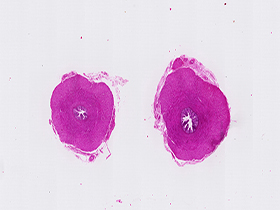

Conducto deferente (tinción H&E)